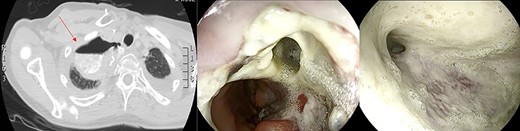

Healthy-appearing granulation tissue and progressive reduction of leak and cavity size.

The patient underwent 14 treatment sessions over 35 days. The leak and the cavity size progressively improved with the development of healthy-appearing granulation tissue s (Fig. 3). Inflammatory indexes and clinical conditions similarly improved. The endoscopic findings were confirmed by CT scans. Complications were not observed.